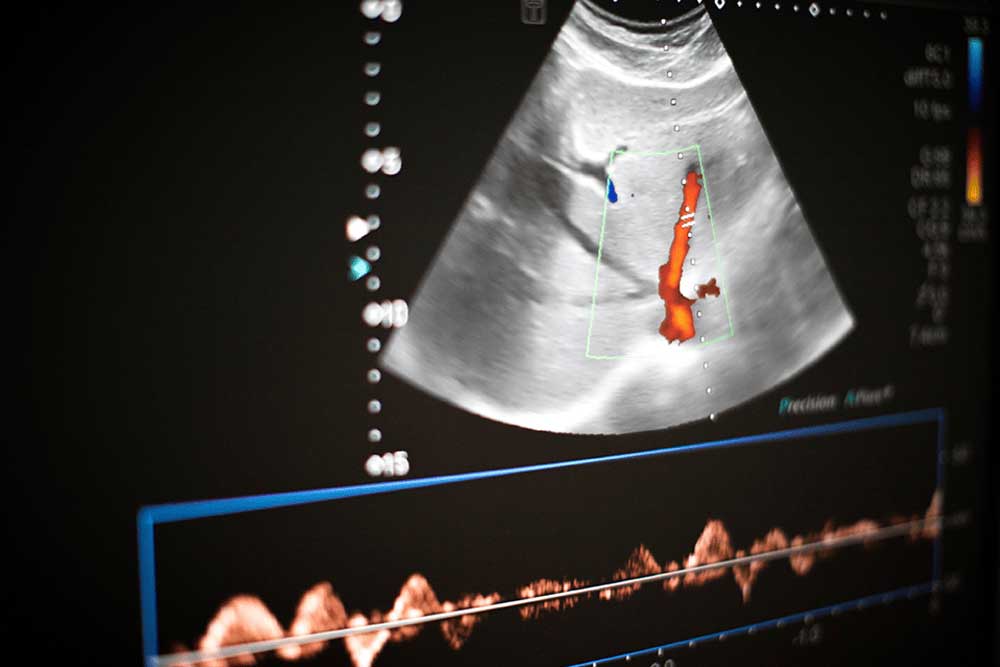

ULTRASONOGRAFÍA

Imágenes de los órganos y tejidos internos del cuerpo obtenidas mediante ondas sonoras de alta frecuencia.

DOPPLER

• Ecografia doppler de vasos abdominales o pelvicos

• Ecografia doppler de vasos